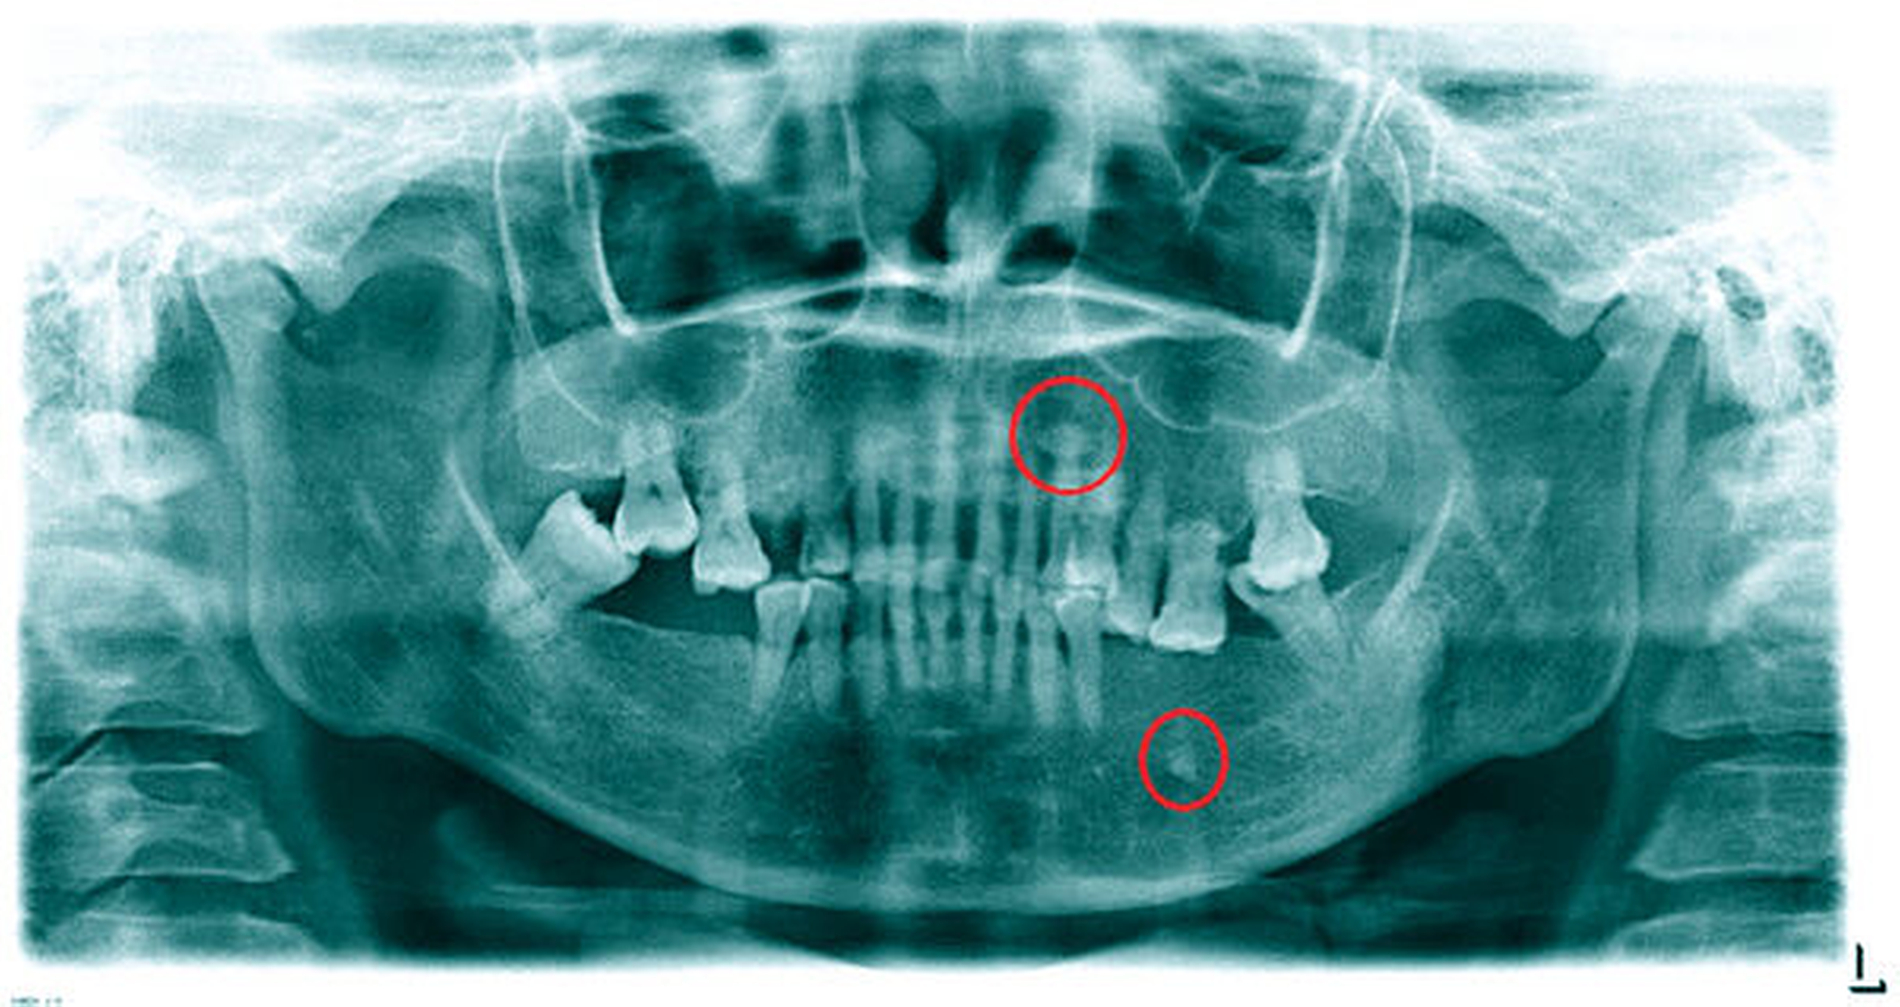

Im Orthopantomogramm (Abbildung 2) stellten sich neben dem aktuellen Zahnstatus zwei rundliche Verschattungen apikal des Zahnes 23 sowie in der Nähe des linken Foramen mentale dar. Das Angio-CT (Abbildung 3) ergab im posterioren Bereich des Zungenkörpers eine Hypervaskularisierung, die bei einer maximalen Abmessung von 2,7 cm x 3,5 cm x 4,8 cm multiple rundliche Verkalkungen im Sinne von intravasalen Phlebolithen einer vaskulären Anomalie aufwies.